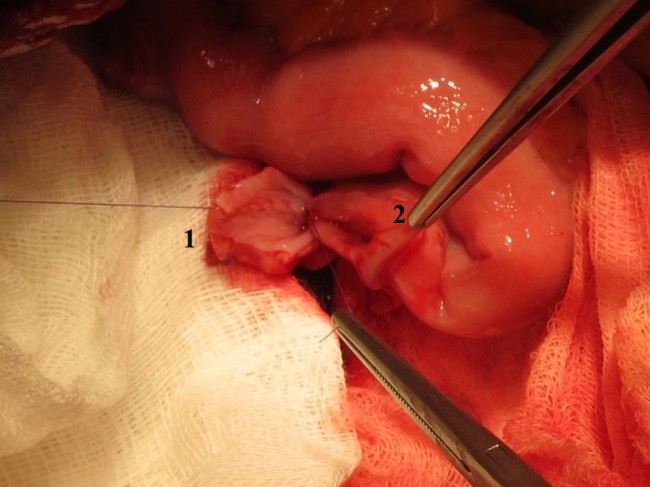

Реконструктивный этап. Для выбора метода реконструкции МП после резекции мы использовали известную схему его сегментарного строения по М.Ф. Поляничко [3]. Если при резекции с клиренсом не менее 2 см от видимого края опухолевой инфильтрации удаляли менее двух сегментов МП, выполняли его ушивание. При более масштабной резекции, а выполняли аугментацию МП участком подвздошной кишки (рис. 2).

Рис. 2. Аугментация мочевого пузыря (А) сегментом подвздошной кишки (Б). В – низведенная сигмовидная кишки. Г – скелетированные наружные подвздошные сосуды.